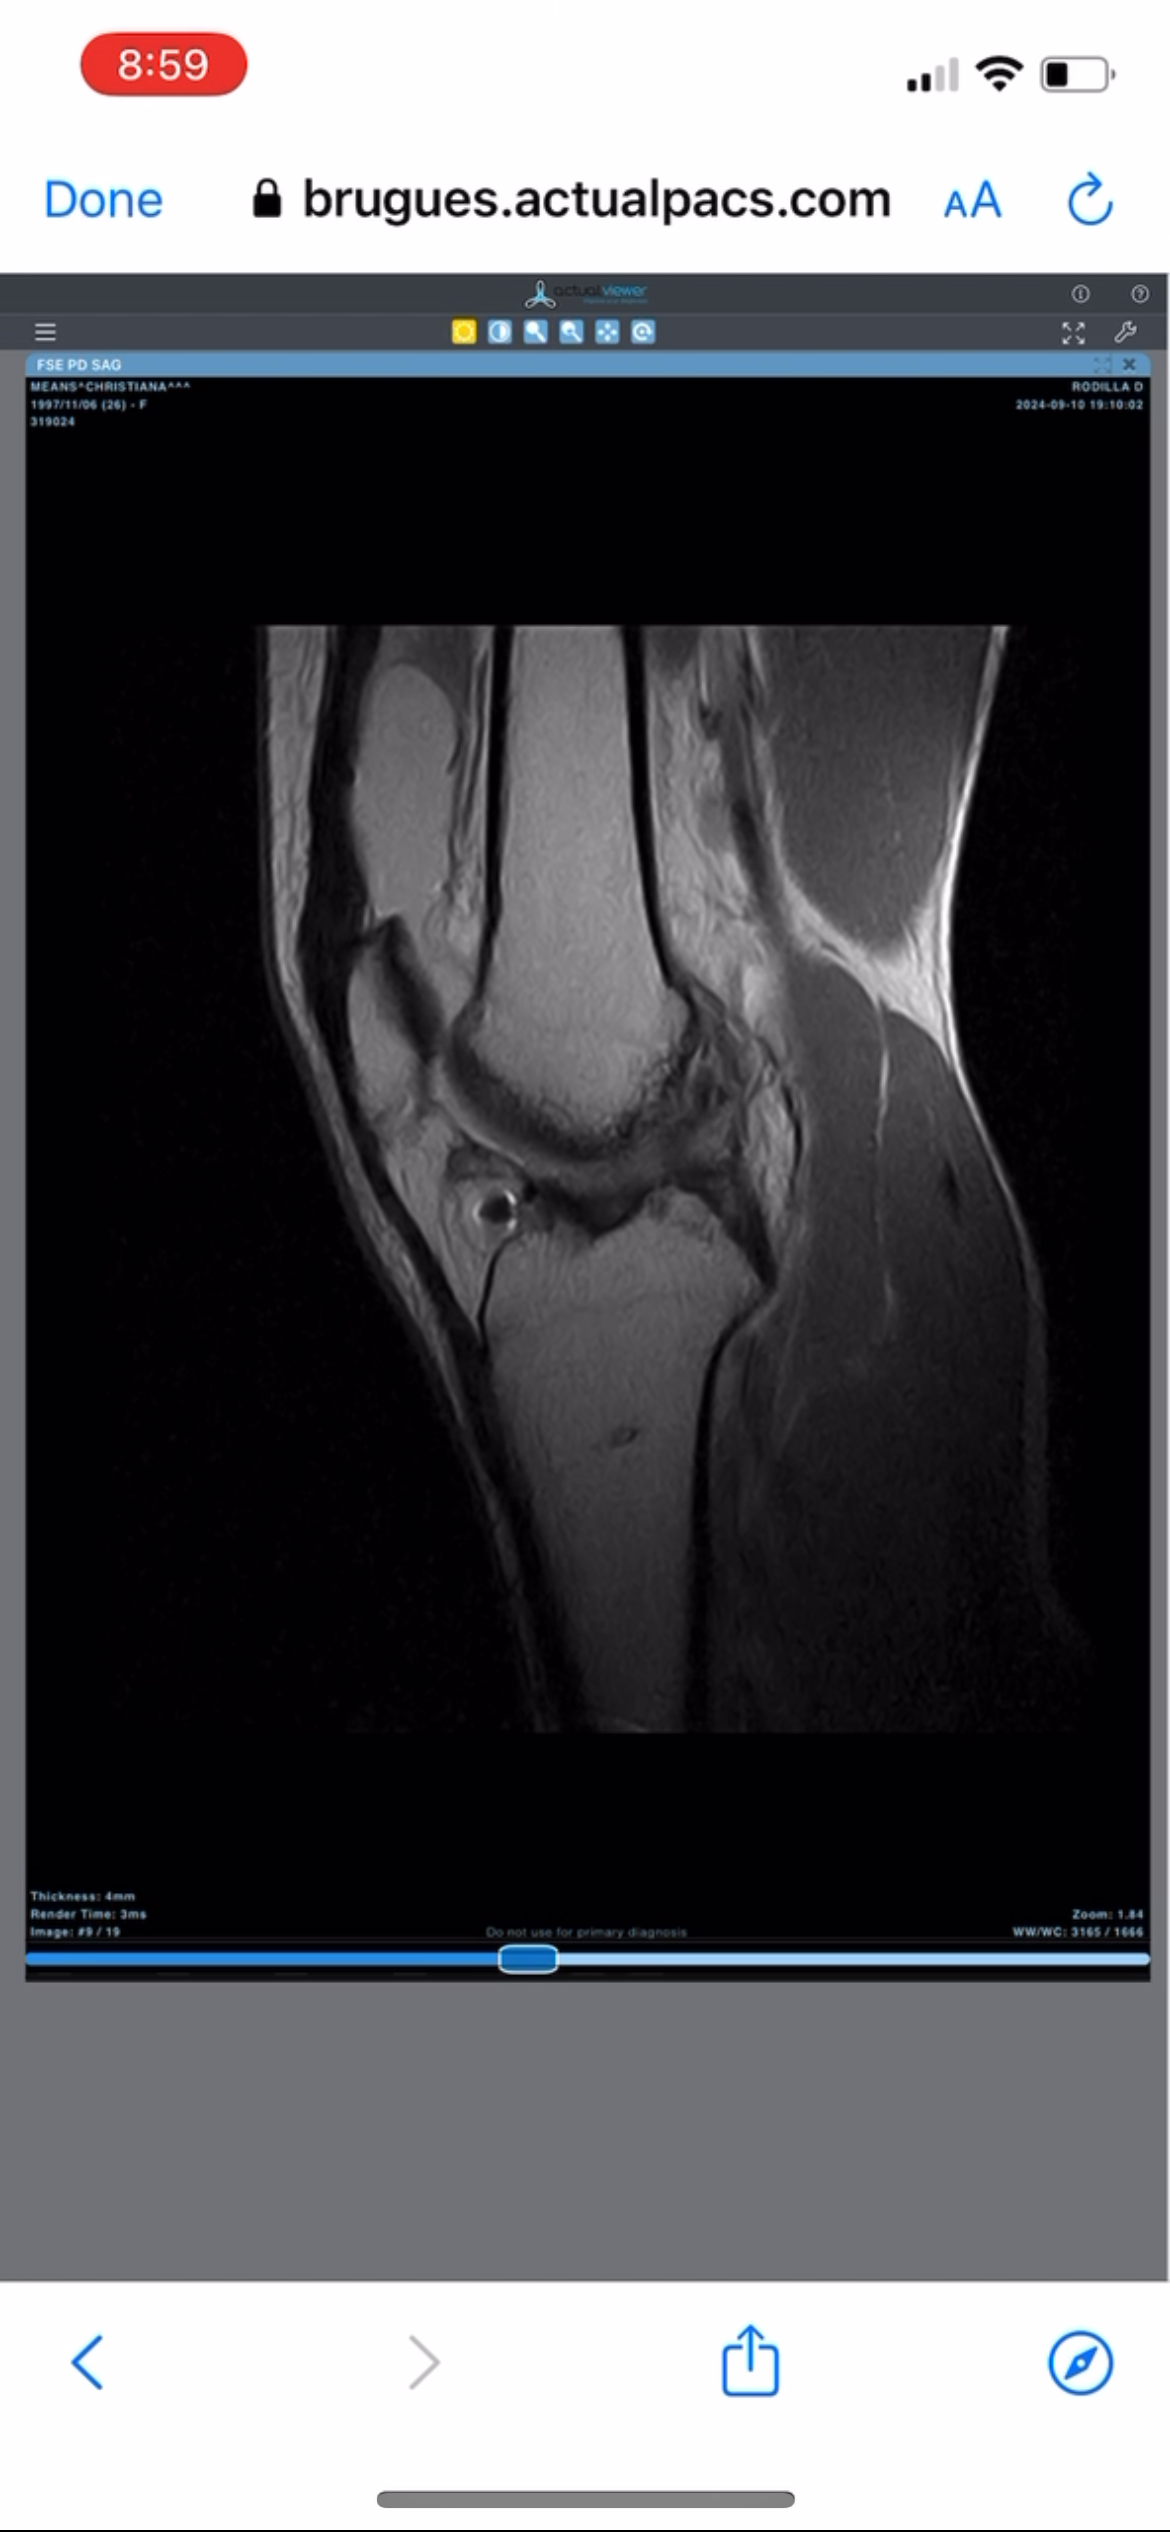

My recent MRI confirmed the worst: No functioning ACL. Multiple meniscus tears. And ongoing MCL damage.